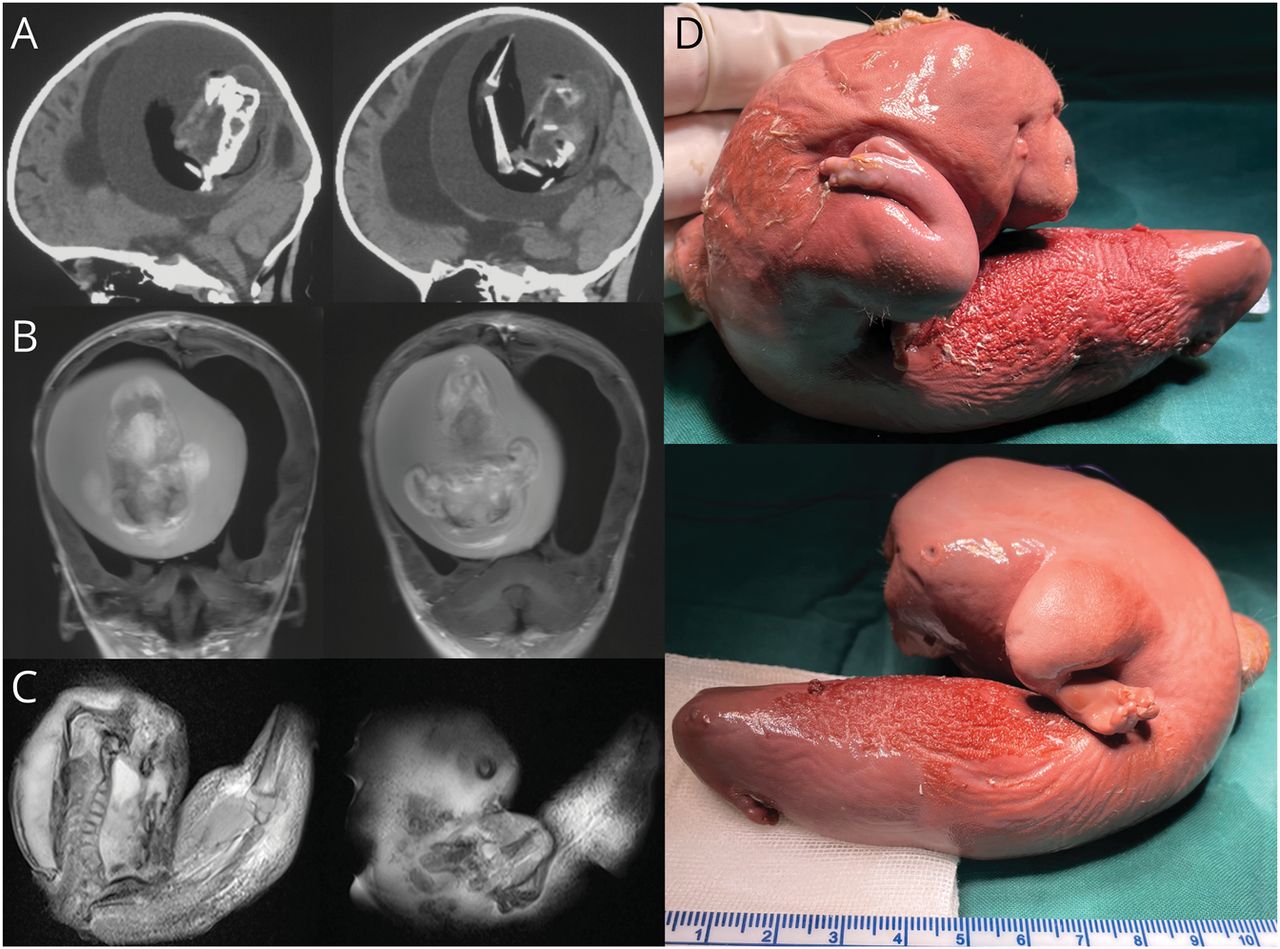

图1

成像的Fetus-in-Fetu

头部CT (A)和t1加权图像(B)的婴儿脑积水,压缩大脑和脊柱脑室质量,股骨和胫骨。t1加权图像质量揭示脊柱裂(C)。fetiform质量与上肢和卫星传回的味蕾(D)。